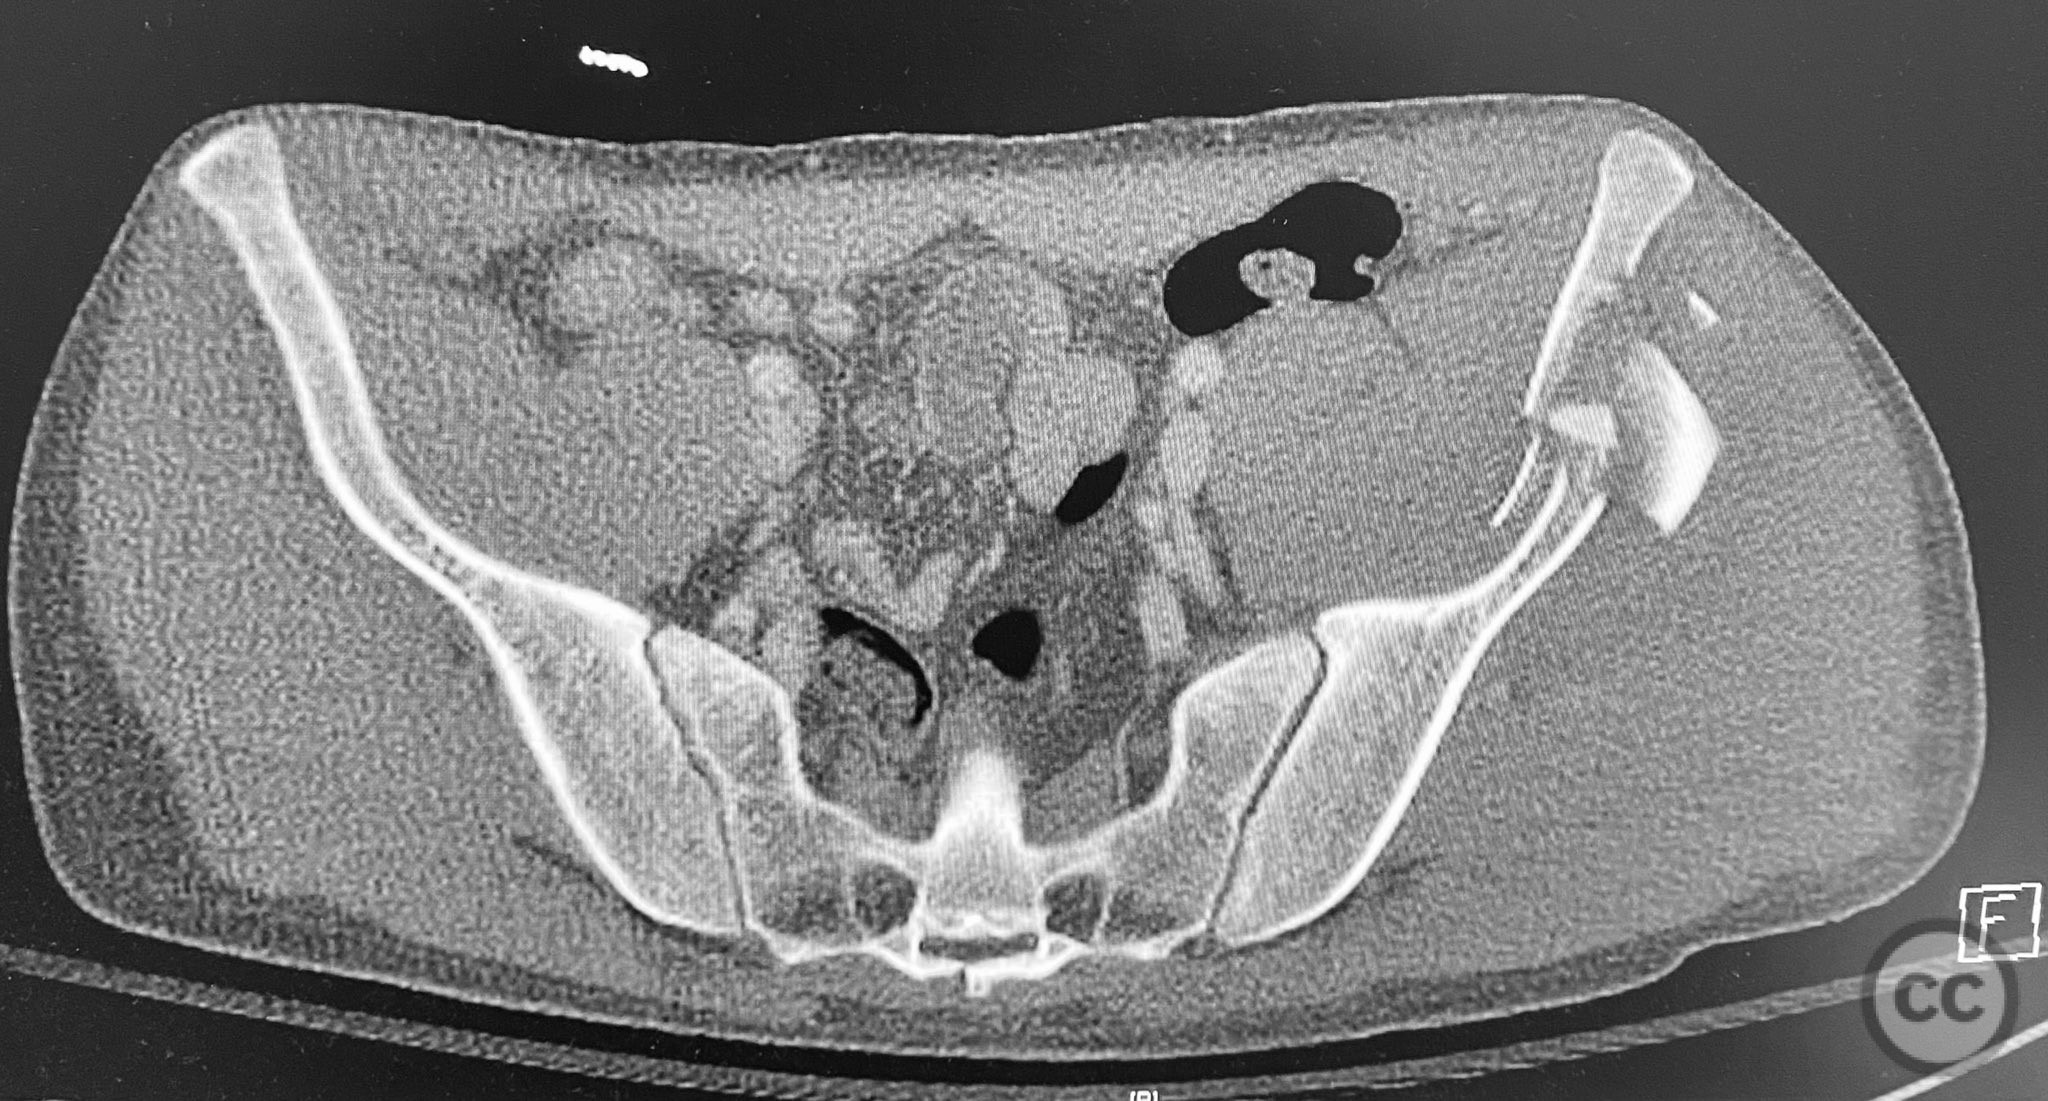

Pelvic Ring - AO/OTA 61x

Pelvis - AO/OTA 6x